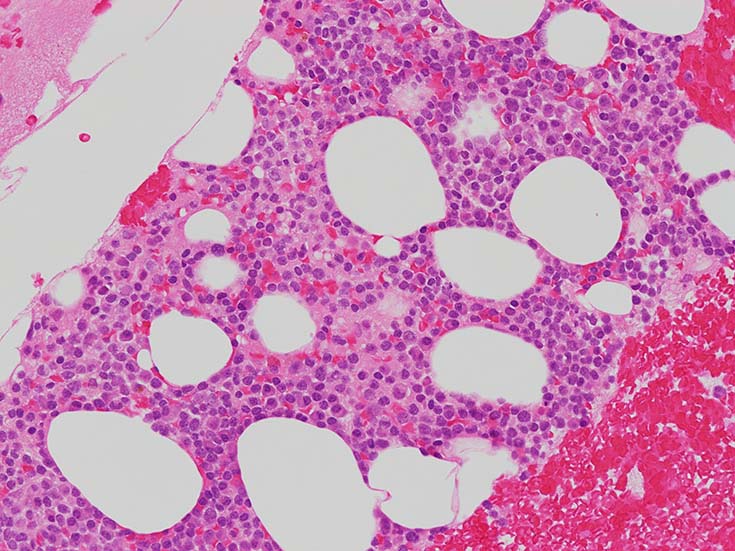

cellularityは60-70%. 赤芽球血島形成はみられない. Naphtol-ASD-CAE染色に赤染される顆粒球系細胞もごくわずか. 成熟Mgkもごく少数で, 正常造血は強く抑制されている.

類円形あるいは, シワのみられるconvolutedな核に核小体をもつN/C比大の細胞が増加している. クロマチンは微細で核は淡明にみえる.Naphtol-ASD-CAE染色陰性.幼若あるいは活性化されたリンパ球様細胞に似ている.

N/C比 70-90%, 中型芽球様細胞が増加. 核は類縁液核網繊細, 明瞭な核小体が 1-数個 細胞質は淡青色 MPO陰性.